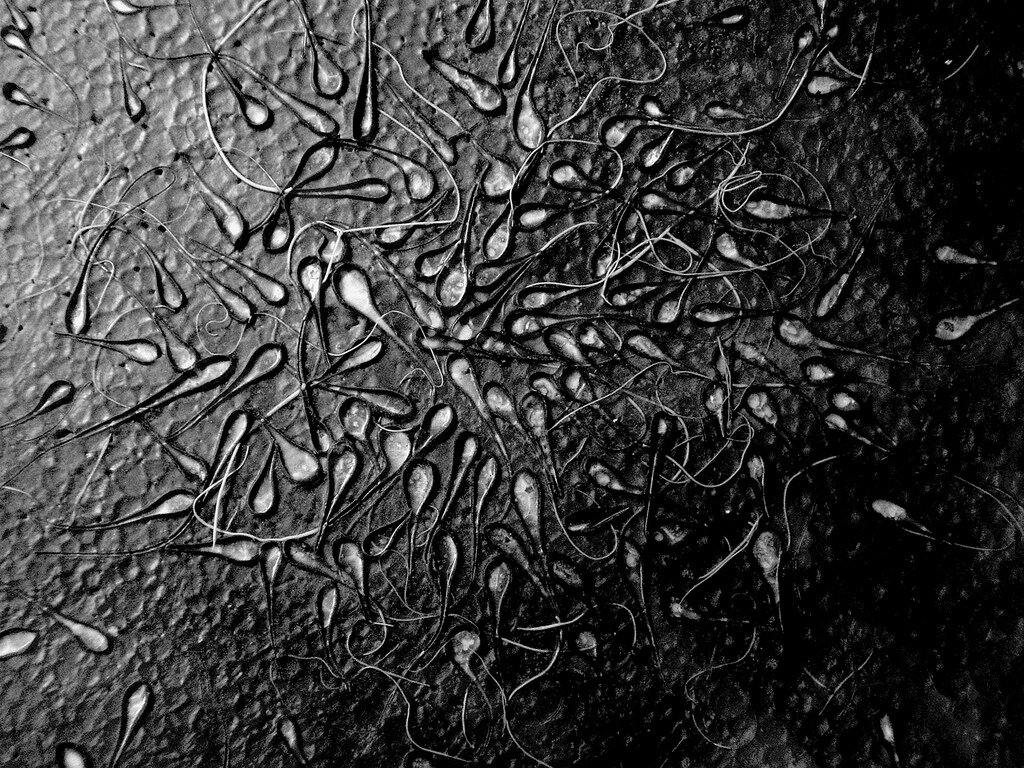

Около 5% мужчин страдают от бесплодия. У 1% отмечается азооспермия — болезнь, при которой в семени нет сперматозоидов. Израильские учёные открыли мутацию в конкретном гене, которая нарушает механизм создания спермы. Исследователи из Университета имени Бен-Гуриона и медицинского центра «Сорока» открыли мутацию в гене TDRD9 , который в норме контролирует механизм созревания и выработки спермы. Мутация блокирует функцию гена и приводит к мужскому бесплодию. Открытие стало возможно благодаря одной бедуинской семье. Пятеро мужчин из этого рода страдали от бесплодия без явной причины. Врачи отобрали и изучили их генетический материал. В результате была обнаружена неизвестная мутация. С новой информацией медики смогут разработать тесты для диагностики бесплодия и создать лекарства на основе редактирования генома.